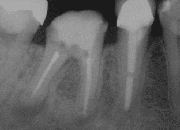

![]() X-ray of a tooth after root end surgery | |

A root end surgery, also known as apicoectomy (apico- + -ectomy), apicectomy (apic- + -ectomy), retrograde root canal treatment (cf. orthograde root canal treatment) or root-end filling, is an endodontic surgical procedure whereby a tooth's root tip is removed and a root end cavity is prepared and filled with a biocompatible material. It is an example of a periradicular surgery.